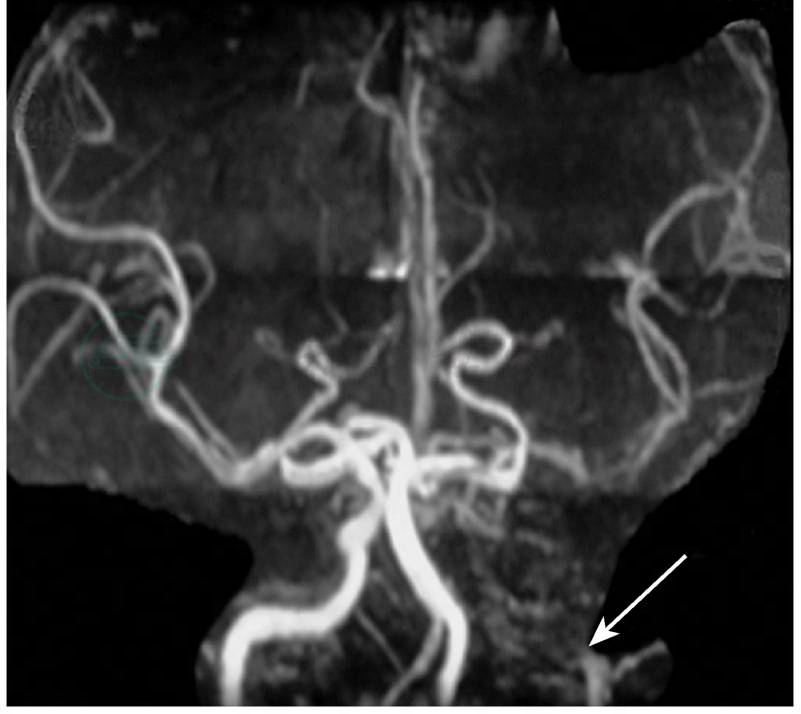

图3 2010年4月22日颅脑MRA显示:左侧颈内动脉颅内段未见明确显影,左侧大脑中动脉较右侧显影浅淡,分支较右侧少(箭头)